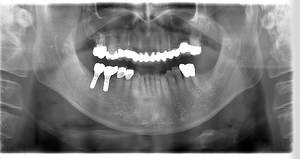

レントゲン写真

- Befor

- After

| 年齢 | 50代・男性 |

| 主訴 | 左上7番 左下5番7番 |

| 治療内容 | ・インプラント埋入 ※1:GBR(骨造成)・・・骨再生誘導法。骨の高さや厚みを人工骨や人工膜などを使用し再生する方法 |

| 治療費 | 合計:1,809,500円(税込) ■内訳 ・左上7番 ・左下5番7番 |

| 治療期間 | 左上7番約1年 左下5番7番約10ヵ月 |

| 治療方針 | 左上7番は昔他院で被せものをしており、被せものの中が歯ぐきの中まで虫歯になっていたため抜歯せざるを得ない状態だった。抜歯と同時に骨造成を行い、骨が出来るまで4ヵ月待ってからインプラントを埋入した。 ※2ポンティック・・・歯のない部分を補うダミーの歯。 |

| 担当者所見 | 元々金属の被せものが多く入っていたため、2次カリエス※3が多かった。今回は金属ではなく、ジルコニアを使用し、2次カリエスにならないよう、患者様にはブラッシング指導とメンテナンスの重要性をお伝えした。 ※3二次カリエス・・・詰め物や被せものを入れた歯が虫歯になること。 |